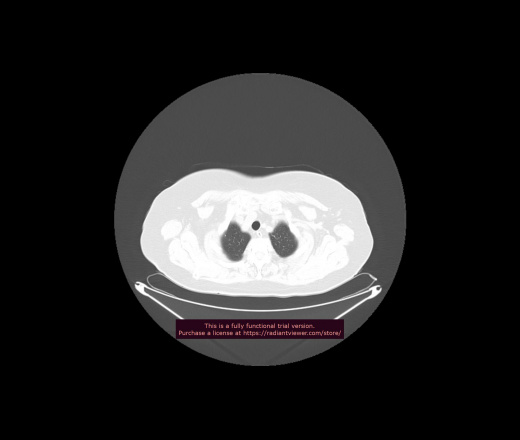

Уважаемые коллеги, если имеется интерес, сможете ли Вы спрогнозировать дальнейшее +-одинаковое течение процесса у 4 данных разных пациентов? Зацепиться где-то можно очень просто, где-то нельзя.